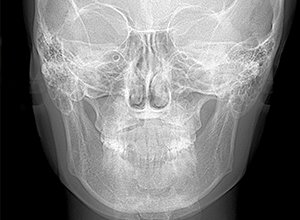

X-Ray所見

セファロ所見 Or-R平面からRは上方に位置づいている。中顔面部の奥行きはあるもののNasionからA点までは距離があるため、下顎は後下方へ回転している。

パノラマ所見 左右上5、左下5に歯根の湾曲が認められた。上下顎左右側8は抜去済みであった。